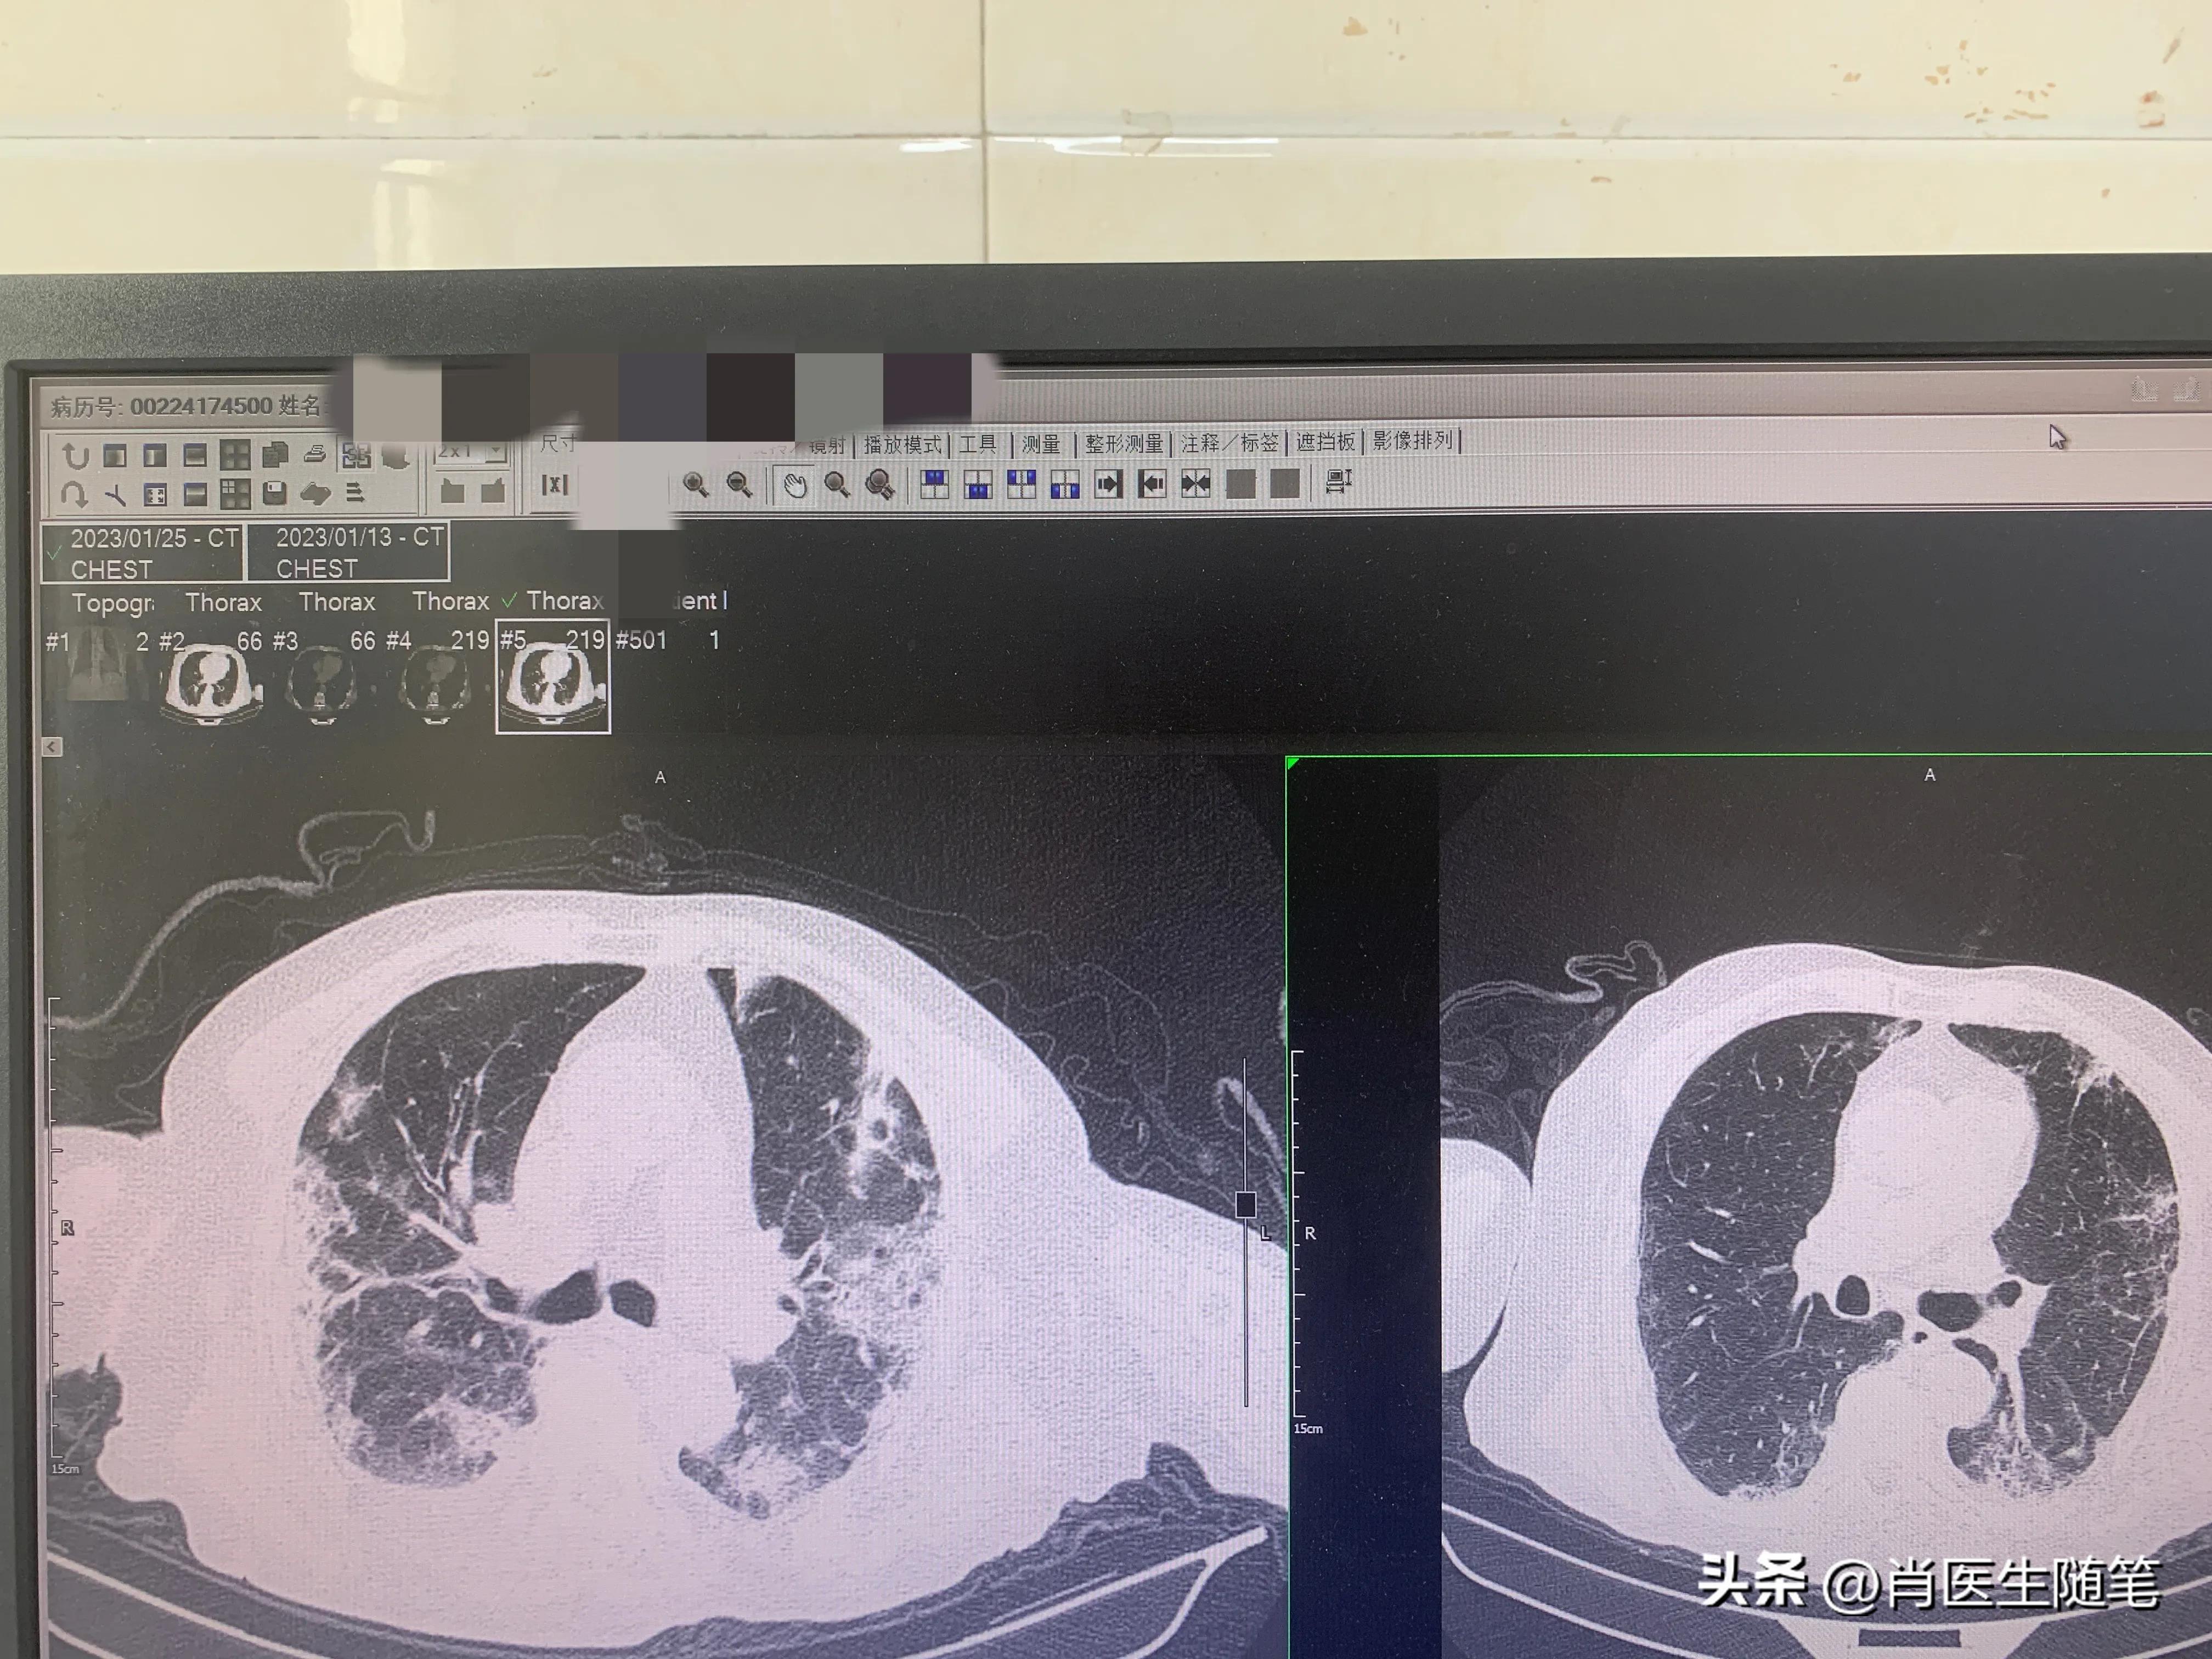

入院后2023-01-13胸部CT提示双肺炎症,纵膈多发淋巴结显示,部分钙化,双侧胸腔积液,心包积液。血提示炎症指标升高,白蛋白略低,33g/l。血氧饱和度吸氧下95%。

治疗后(2023-01-25)复查胸部CT,炎症较前吸收,下图是同样切面对比图。左边是13号的,右边是25号的。